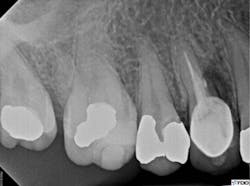

The access cavity and canal walls were examined for fracture or perforation. While a fracture was not observed, a perforation was visualized at the apical extent of the post preparation in the lingual canal. Conventional re-treatment of both the buccal and lingual canals was completed. Careful attention to the irrigation protocol was made in order to prevent extrusion of irrigating solutions outside of the perforated root. The buccal canal was obturated to the canal orifice, and the lingual canal was packed apical to the perforation. A small piece of absorbable collagen material (OraTape, Salvin Dental) was packed into the perforation until a matrix was formed that would keep the repair material confined to the root. The perforation and coronal third of the lingual canal were filled with mineral trioxide aggregate (MTA) (figure 4). The occlusal access was sealed with cotton and Cavit temporary filling material (3M ESPE). The final treatment radiograph shows re-treatment and repair (figure 5).

Figure 5: Final radiograph showing re-treatment and repair